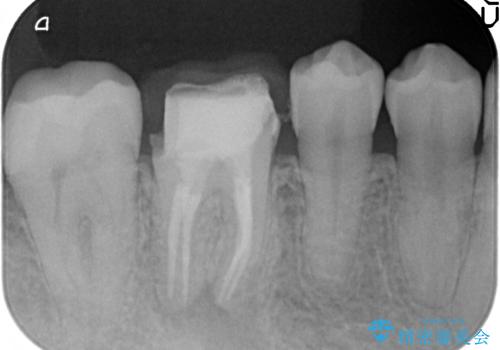

検査の結果X線上で右下6に根尖病変を認めたため、再根管治療を行いました。

症状が治まったのを確認後、オールセラミッククラウンによる補綴を行いました。

今回用いたオールセラミッククラウンはジルコニアフレームという白い素材の上にセラミックを盛っているため、審美性が非常に高いのが特徴です。

また、ジルコニアは人工ダイヤモンドの材料にも使われているほど高い強度を持っており、そのためオールセラミッククラウンは審美性だけでなく、奥歯やブリッジの補綴も可能とするクラウンです。